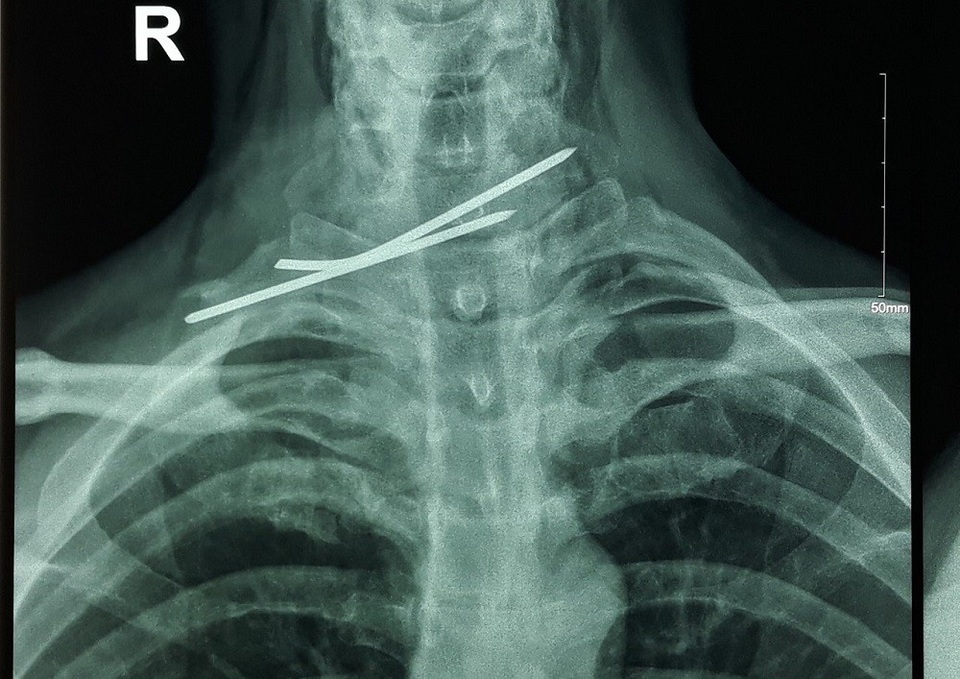

Qua thăm khám và làm các cận lâm sàng như: X quang ngực, CT scan, nội soi thực quản. Bệnh nhân được chẩn đoán, dị vật vùng cổ do đinh Kirschner đâm xuyên thực quản và khí quản. Sau khi có kết quả cận lâm sàng, các bác sĩ đã tiến hành phẫu thuật lấy đinh (khoảng 90cm) và khâu lại thực quản, khí quản.